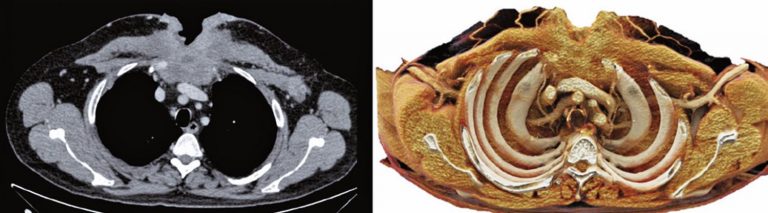

Cinematic rendering for three-dimensional reconstructions of the chest wall: a new reality

DOI: 10.31744/einstein_journal/2020MD5223

ABSTRACT Computed tomography with multiple detectors and the advancement of processors improved rendered images and three-dimensional reconstructions in clinical practice. Traditional axial slices form non-intuitive images because they are seen in only one plane. The three-dimensional reconstructions can show structures details and diseases with complex anatomy in different perspectives. Cinematic rendering is a newly three-dimensional reconstruction technique, already approved for clinical use, which can produce realistic images from traditional computed tomography data. The algorithm used is based on light trajectory […]

Keywords: Image processing, computer-assisted; Tomography, x-ray computed